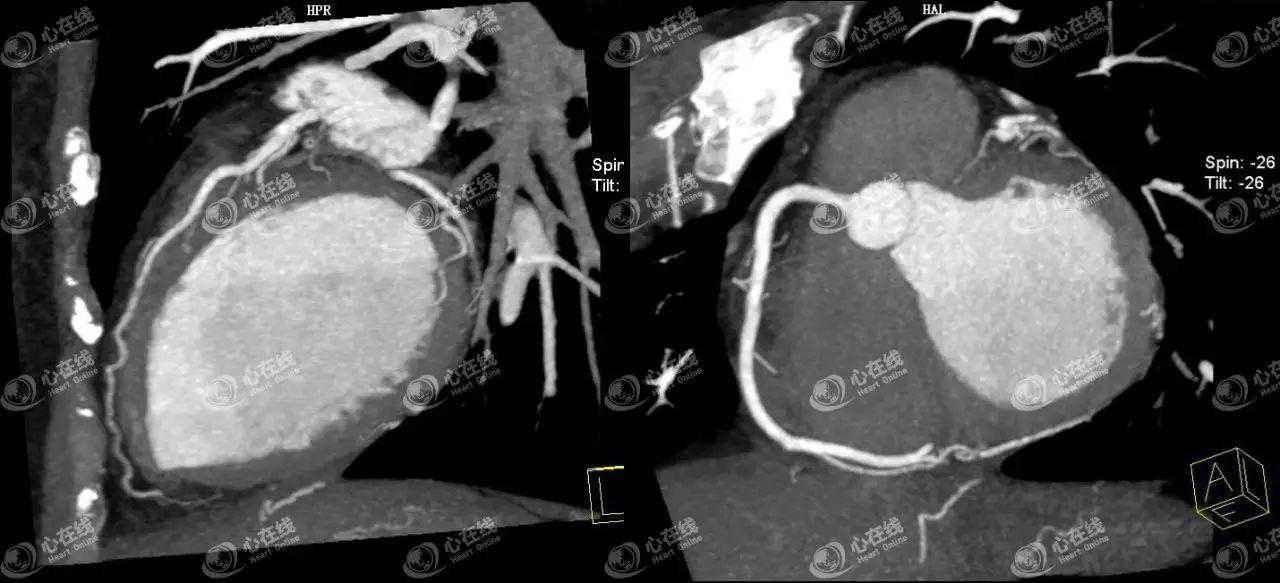

进一步查心脏超声、心脏增强核磁、冠状动脉CTA(图2)、主动脉CTA、肺动脉CTA均未见明显异常。

图2